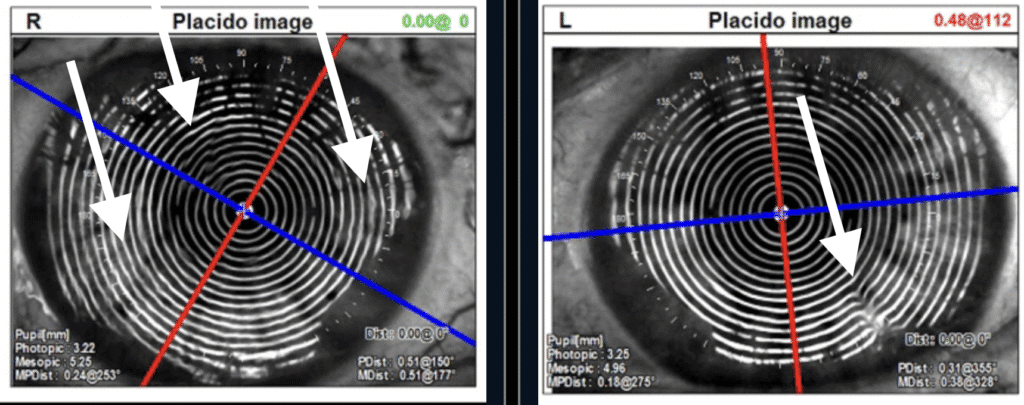

Corneal With-the-rule Astigmatism in both right and left eyes.

Arrows point to areas of surface irregularities of the tear film and/or corneal surface.